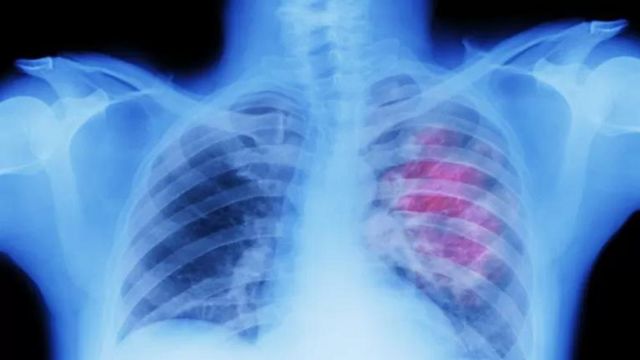

10. Kikohozi cha kudumu au sauti ya kukwaruza

Kikohozi cha kudumu kinaweza kuwa ishara ya saratani ya mapafu.

Inashauriwa kumtembelea daktari ikiwa tumekuwa tukiugua kwa zaidi ya wiki tatu.

Hii hutokea mara nyingi zaidi katika saratani ya kongosho, tumbo, umio, au mapafu.